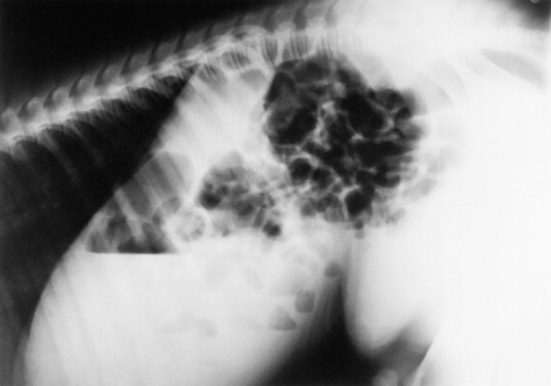

Skeletal maturity is assessed by radiographing a carpus and a tarsus for evidence of incomplete ossification (Fig. 19-1). Accelerated ossification does not appear to be a feature of foals born prematurely after exposure to chronic in utero stress. Incomplete ossification coupled with periarticular laxity predisposes the premature or dysmature foal to long-term skeletal problems. Foals with incomplete ossification and more than 30% reduction of the central and/or third tarsal bones with pinching or fragmentation of the dorsal aspects of affected bones commonly develop degenerative joint disease and have a guarded prognosis for future athletic performance. Restriction of exercise is recommended in order to minimize collapse of developing carpal or tarsal bones, but forced recumbency may predispose the foal to or exacerbate pulmonary disease. Furthermore, normal load bearing encourages ossification. Periarticular laxity predisposes the premature foal to angular limb deformities that facilitate abnormal load bearing and increase the risk of cuboidal bone crush injury of the carpus or hock. Splinting and attention to hoof care are recommended if angular limb deviation develops. In most cases flexural deformities and laxities improve over time. Dorsal splints are recommended for flexural deformities involving the fetlock, and heel extensions are helpful to foals with flexural laxity.

Fig. 19-1 A, Lateral tarsus of a 1-day-old, 305-day gestational age colt. Note the lack of ossification of the small tarsal bones. B, Lateral tarsus of the same foal as in A, at 3 weeks of age, showing irregular ossification. Without the initial radiograph, increasing ossification could have been confused with bone lysis and osteomyelitis. The foal is reported to be sound at 6 months of age.